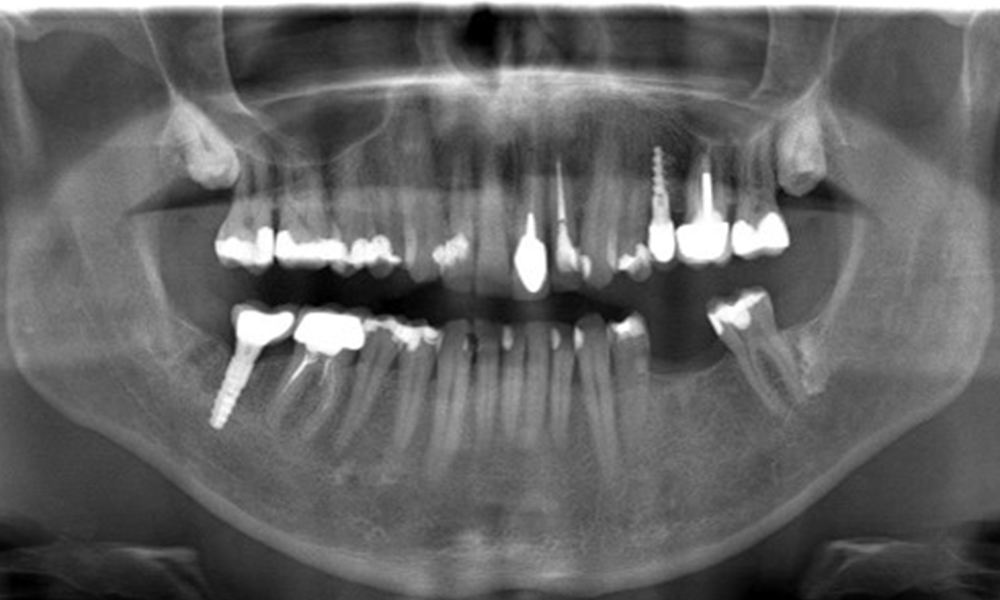

Der Patient hat einige zahnärztliche Restaurationen und zwei Implantate (2. und 4. Quadrant). Anhand der aktuellen Befunde lässt sich eine Gingivitis bei stabilem parodontalen Zustand am reduzierten Parodont (Stadium III, Grad A) feststellen.

Versorgungen: zahnärztliche Restaurationen (NEM keramisch verblendet), zwei Implantate (2., 4. Quadrant)

Der Patient zeigt keine besonderen Risikofaktoren mit spezifischen zahnmedizinischen Auswirkungen. Daher ist der aus der Mundgesundheit ermittelte Bedarf maßgebend. Hierbei zeigt sich eine gute Mundgesundheit mit stabilem, reduzierten Parodont. Sollte sich bei einem Kontrolltermin am Implantat eine Vergrößerung von ST im Vergleich zur Baseline kombiniert mit einer diffusen Blutung zeigen, so sollte eine Röntgendiagnostik (i. S. eines Zahnfilms) erfolgen, um frühzeitig einen periimplantären Knochenverlust zu erkennen und dagegen zu intervenieren.